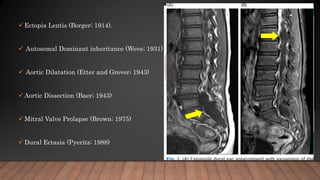

 Ectopia Lentis (Borger; 1914).

 Autosomal Dominant inheritance (Weve; 1931)

 Aortic Dilatation (Etter and Grover; 1943)

 Aortic Dissection (Baer; 1943)

 Mitral Valve Prolapse (Brown; 1975)

 Dural Ectasia (Pyeritz; 1988)